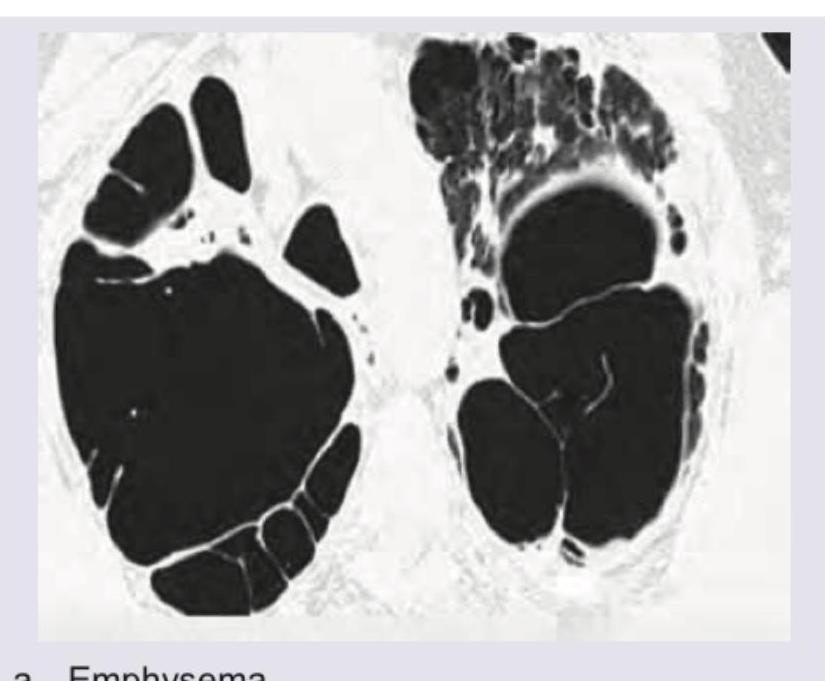

The CT chest of a patient given below shows presence of: (Recent NEET Pattern 2016-17)

Explanation: ***Emphysema*** - The CT image displays numerous large, thin-walled **air-filled spaces** or **bullae** within both lung fields, consistent with severe emphysema. - These areas represent the destructive enlargement of airspaces distal to the terminal bronchioles, a hallmark of **emphysema**, often leading to significant loss of lung tissue. - Key feature: **destruction of alveolar walls** with coalescence into larger air spaces without visible walls. *Artifact* - An artifact would typically manifest as streaking, blurring, or other distortions that do not conform to anatomical structures or known pathologies. - The findings here are well-defined, anatomically localized spaces, representing a true pathology rather than an imaging error. *Silicosis* - Silicosis is characterized by **nodular opacities**, interstitial fibrosis, and sometimes mass-like lesions (progressive massive fibrosis), not large emphysematous bullae. - The primary findings in this CT are clearly destructive airspaces, not the fibrotic or nodular changes typical of silicosis. *Bronchiectasis* - Bronchiectasis shows **dilated, thick-walled airways** with a "tram-track" or "signet ring" appearance. - Unlike emphysema, bronchiectasis involves bronchial wall thickening and the cystic spaces are airways, not destroyed alveolar tissue. - The thin-walled bullae in emphysema lack the prominent wall thickening seen in bronchiectasis.